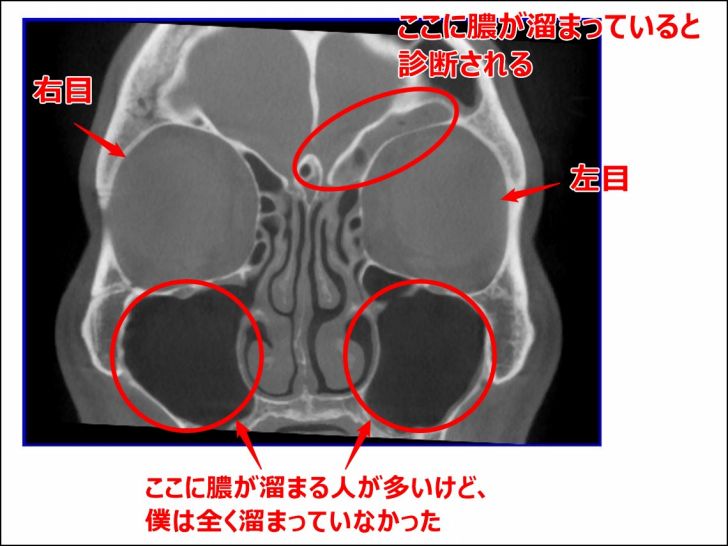

実際の自分のCT画像です。

2015年5月の副鼻腔

まずは一度目の手術を行う前の、何も処置をしていない僕の副鼻腔のCT画像です。

▼2015年5月のCT画像

慢性の副鼻腔炎であることが分かっている程度で、とにかく頭痛がひどかった時期です。

画像右上の部分(前頭洞)が灰色になっていて、そこに膿が溜まっていました。

【画像解説】

あくまで病院の先生に聞いた話をまとめているだけですが、左目の上に膿が溜まっていて炎症を起こしており、それが頭痛の原因でした。

良く膿が溜まると言われている上顎洞(じょうがくどう)と呼ばれるところには、全くと言っていいほど膿はありませんでした。

[/su_note]